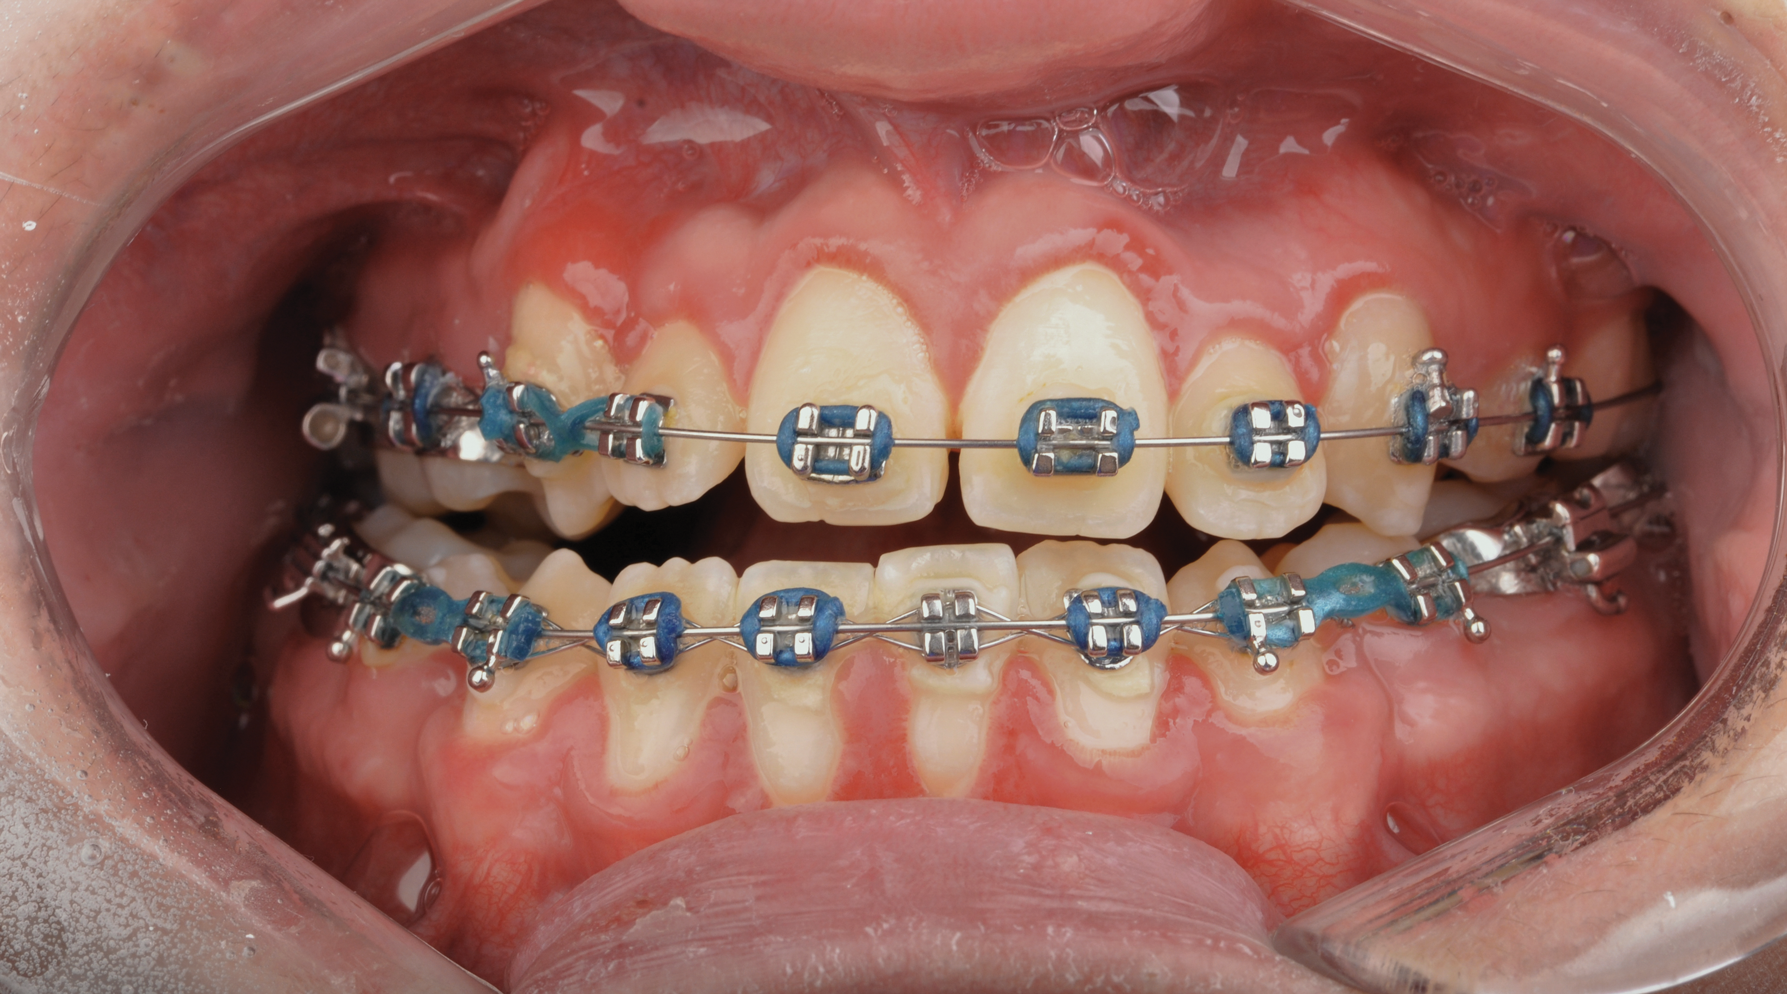

Fig 18. Bite interdigitation to finalize surgical orthodontic correction. After orthodontics, periodontal plastic surgery, bleaching, microabrasion, and restorative dentistry were performed.

Fig 19. Bite interdigitation to finalize surgical orthodontic correction. After orthodontics, periodontal plastic surgery, bleaching, microabrasion, and restorative dentistry were performed.

Fig 20. Bite interdigitation to finalize surgical orthodontic correction. After orthodontics, periodontal plastic surgery, bleaching, microabrasion, and restorative dentistry were performed.